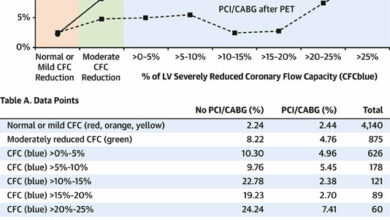

A new therapeutic target for the prevention of heart failure due to aortic stenosis

Cardiomyocyte-specific human β3AR overexpression prevents cardiomyocyte hypertrophy upon catecholamine challenge via NO/cGMP pathway. A Genetic constructs for adeno-associated virus (AAV)…